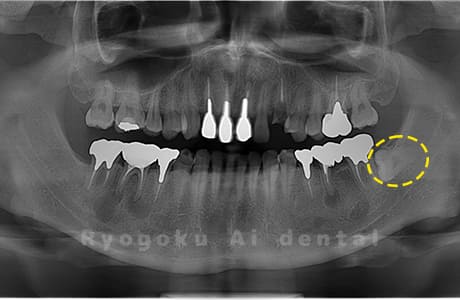

Case24

- 原因

- 下顎左右の埋伏の親知らず

- 治療内容

- インプラント治療は他院でおこなっており、当院で下顎左右の埋伏の親知らずを抜歯したケースです。

<リスク・副作用>

手術後は痛み、腫れ、痺れなどの副作用が生じる場合があります。